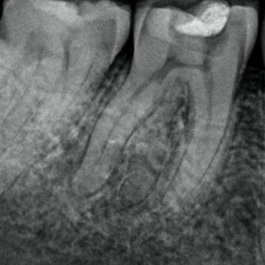

Radiographs and CBCT

It is important to assess radiographs carefully for the presence of extra roots.

In radix entomolaris, the disto-lingual root often lies on the same bucco-lingual plane as the main distal root.

This superimposition can ‘hide’ the root, making it difficult to identify. Therefore, a parallax radiograph (taken from a 30 degree mesial or distal angulation) is helpful.